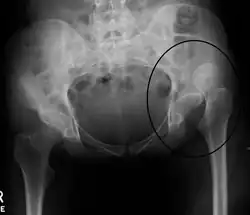

Anterior dislocations happen with trauma forcing external rotation and abduction of the hip.[4][5] In the setting of forced external rotation and abduction of the hip, the hip flexed and extended leads to the inferior and superior sub-types of anterior hip dislocation, respectively.[4][5] Hip dysplasia also makes one more susceptible to hip dislocation.[22] Hip dysplasia is a congenital condition in which the hip is deformed in a way that decreases the congruency between the head of the femur and the acetabulum of the pelvis.[22] Bony congruence is a stabilizing factor to the hip joint, so the decrease in this conferred by hip dysplasia makes one more susceptible to dislocation.[22]

An anterior-posterior (AP) X-ray of the pelvis and a cross-table lateral X-ray[24] of the effected hip are ordered for diagnosis.[4][5][16] The size of the head of the femur is then compared across both sides of the pelvis. The affected femoral head will appear larger if the dislocation is anterior, and smaller if posterior.[7] A CT scan may also be ordered to clarify the fracture pattern.[20]